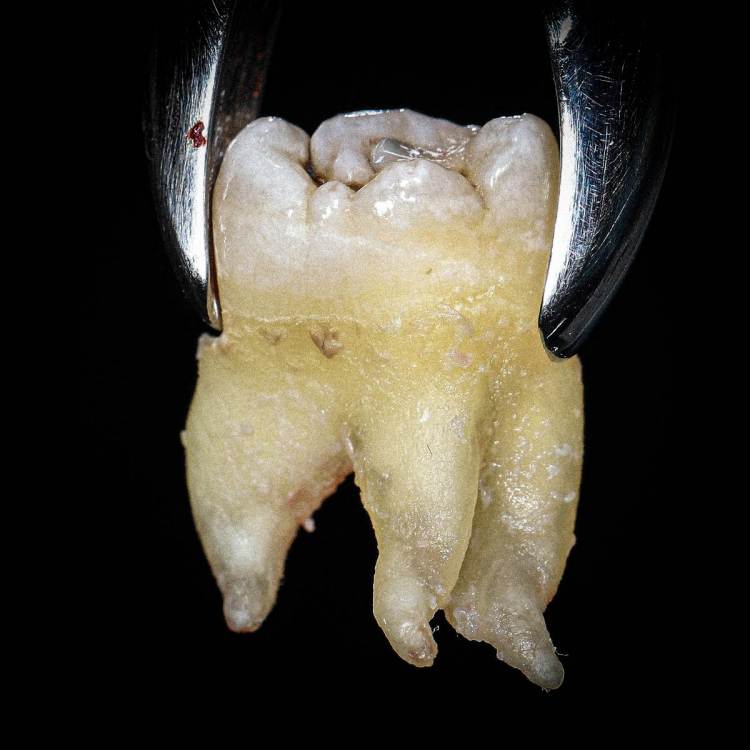

shishok Опубликовано 14 июня, 2020 Поделиться Опубликовано 14 июня, 2020 В пятницу удаляла 18 младшему сыну.По снимку-3 корня,по факту-5(+ маленький приросший к шейке). 1 Ссылка на комментарий